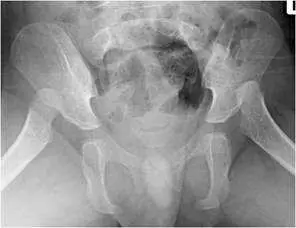

第二張(另一角度或局部放大觀):

- 可見骨盆及股骨近端,呈現雙側股骨頭相對於髖臼的位置異常,股骨頭位置偏外上方。

- 髖臼窩淺,股骨頭覆蓋率不足,與發育性髖關節發育不良(developmental dysplasia of the hip, D